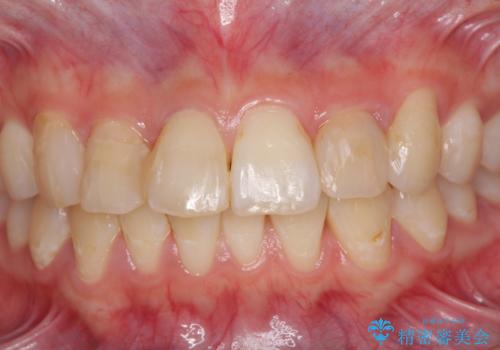

- コンポジットレジンによる治療で継ぎ接ぎだらけになってしまった前歯を綺麗にしたいとのことで来院された患者様です。

必要に応じて根管治療を行い、前歯6歯をオールセラミッククラウンで補綴することとしました。

治療途中に出産を迎えるため、下顎前歯のデコボコを部分矯正で改善し、上下前歯を綺麗に仕上げることとしました。